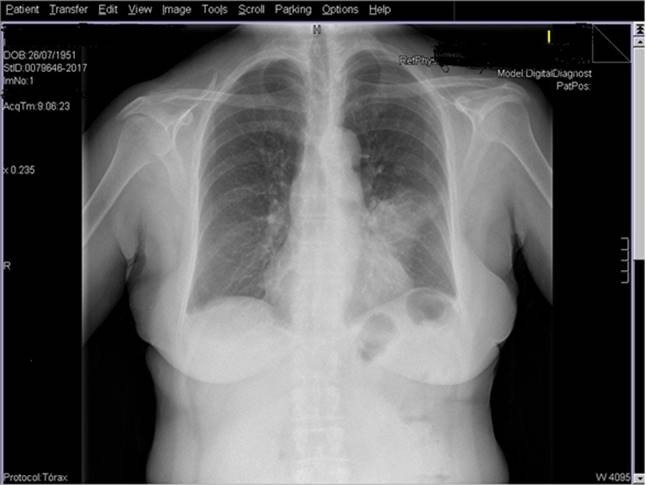

Se realiza radiografía de tórax (Figura 1) en la que se objetiva un infiltrado a nivel de la língula. Ante el diagnóstico de neumonía se comienza tratamiento antibiótico con levofloxacino 500 mg/día durante 7 días. La sintomatología desaparece y la paciente queda asintomática, pero un mes después la imagen radiológica persiste, por lo que se decide realizar TAC torácico. En esta prueba radiológica se observa una atelectasia segmentaria en la língula, con imagen pseudonodular de 1,2 cm en el hilio izquierdo. Ante este hallazgo se decide realizar una broncoscopia, objetivándose una lesión que obstruye por completo la entrada del fibrobroncospio (Figura 2), por lo que se procede a realizar exéresis completa. La anatomía patológica es compatible con un hamartoma condromatoso.